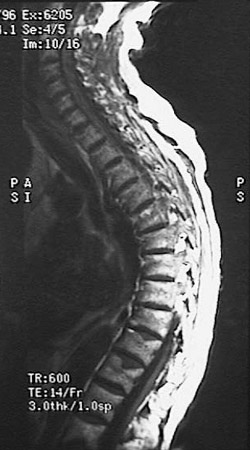

This MRI of the spine demonstrates marked kyphosis with

compressed fractures

. Such a finding can be seen as a consequence of osteoporosis.